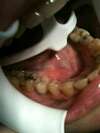

Mise en place de la couronne